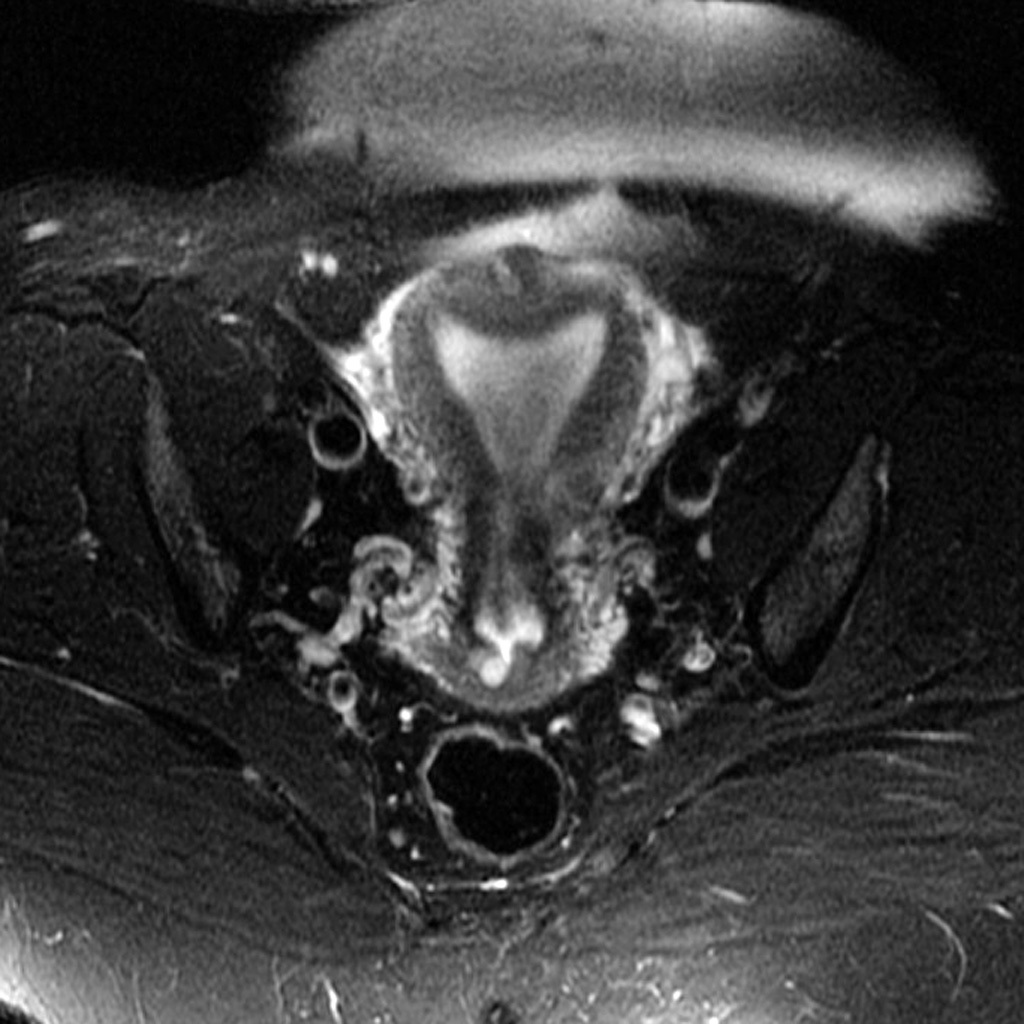

Dx?

Arcuate uterus

(Notice fundus is enlarged but otherwise structurally normal)

Pathogenesis?

Failure of medial walls of caudal portion of Mullerian ducts to resorb